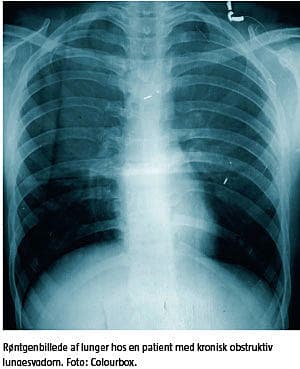

KRONISK OBSTRUKTIV LUNGESYGDOM

KOL er en inflammatorisk sygdom, som overvejende er medieret af neutrofile granulocytter og makrofager. Den inflammatoriske proces forværres i forbindelse med infektion, både viral og bakteriel, og især efter virale infektioner er eosinofile granulocytter til stede i luftvejene. Bakteriel kolonisering i de nedre luftveje er endvidere associeret med øget luftvejsinflammation og forekomst af eksacerbationer [1].

Behandlingen af KOL består primært af rygestop, fysisk aktivitet og medicinsk behandling i form af langtidsvirkende bronkodilatatorer og inhalationssteroid, som medvirker til at reducere antallet af eksacerbationer.